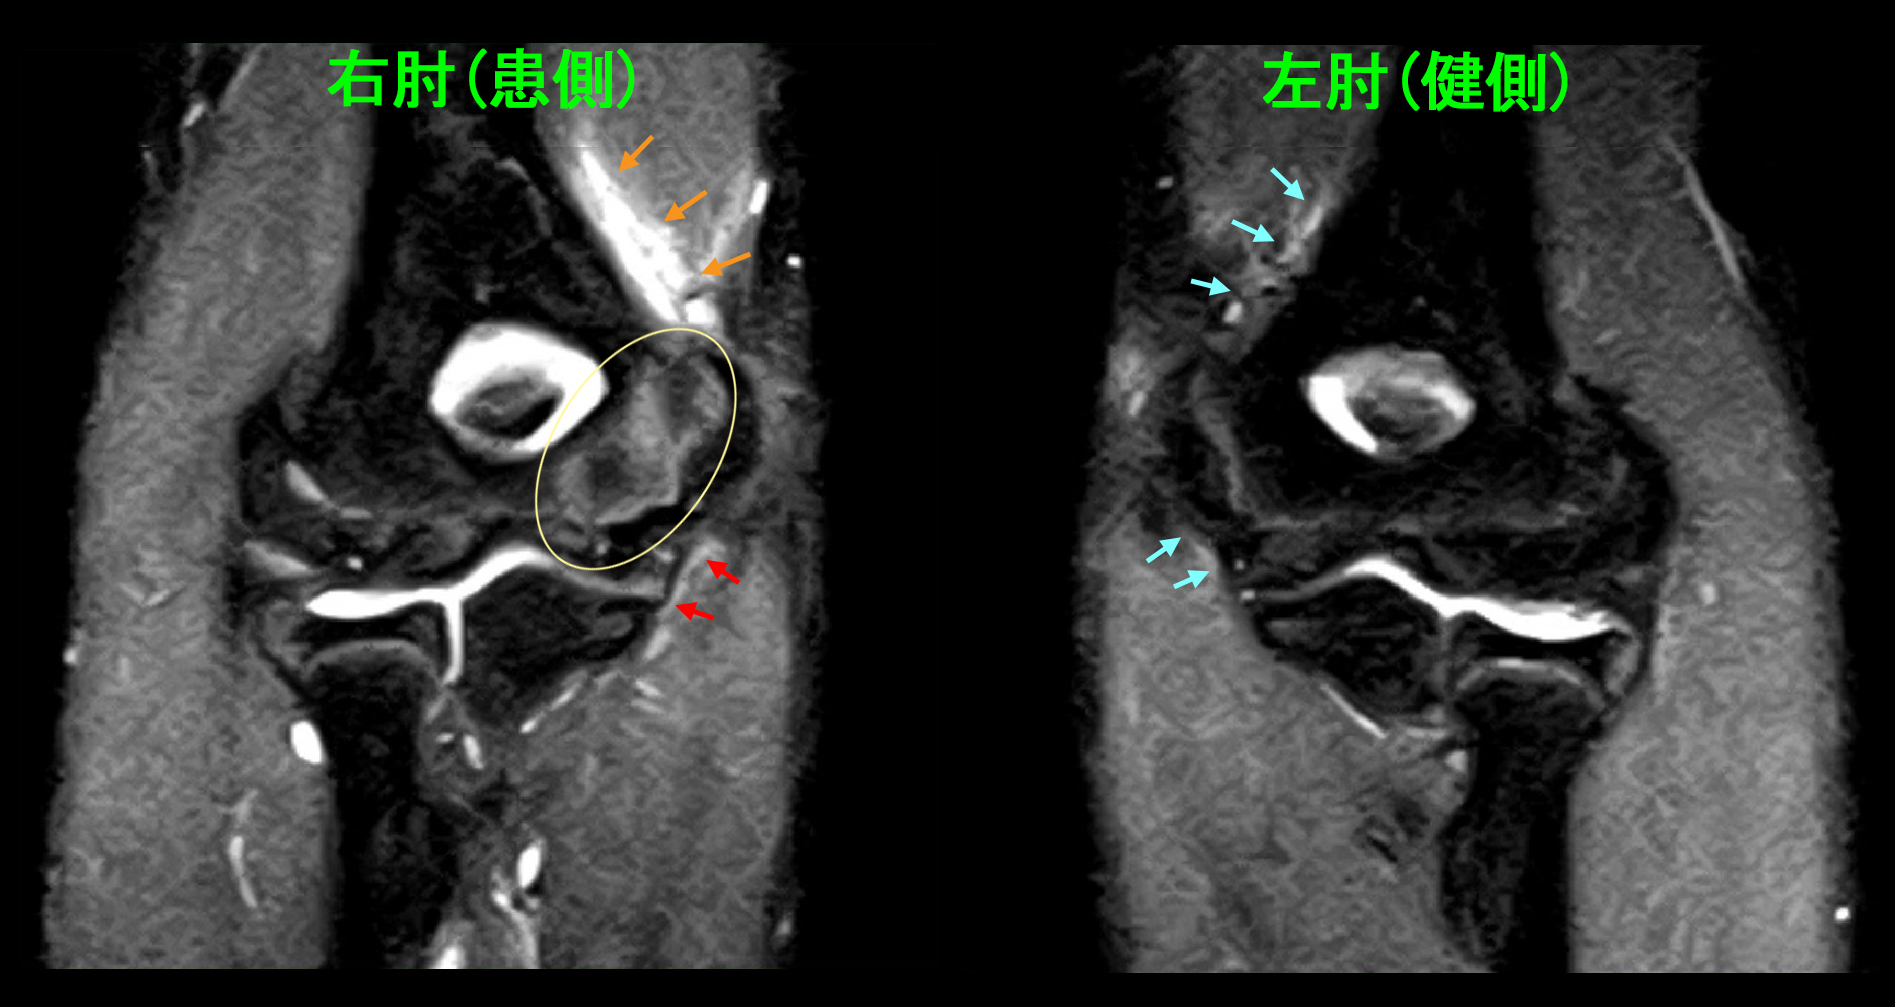

74才の主婦で社交ダンスを週2回行っているMさんです。平成29年10月26日神棚への供え物の際60㎝の脚立から転落し、左膝を打撲したそうです。しかし、その後痛みもなくダンスも続けていたのですが、11月4日(受傷9日後)左膝痛が悪化し階段昇降が困難となり、11月5日に当院を受診されました。理学所見としては左膝外側半月板に圧痛(医師が押してみて痛みが出るかどうかを見る所見です)を認めました。レントゲン像は異常を認めません。赤丸領域に痛みを訴えていました。

74才女 Xp1.jpg

74才女 MR1.jpg

T1というMRI条件での冠状断(前後像)となりますが、赤矢印が本来白い骨が黒くなっており、骨の損傷を示します。骨折です。

74才女 MR2.jpg

T1矢状断(側面像)でも赤矢印が骨折所見です。骨折(骨が損傷)していても、当初はダンスも可能であったのです。私は4週間の安静を指示しましたが、Mさんは12月10日(4週後)にクリスマスのダンス発表会があり、ドレスも購入してしまったと言っていました。私は、「諦めた方が無難ですが、私は私の判断を強制しません。気合いと根性で頑張れそうだったらやってもいいのではないですか。Mさん次第です。」と述べました。Mさんはダンス発表会にも出場して、問題なかったと教えてくれました。